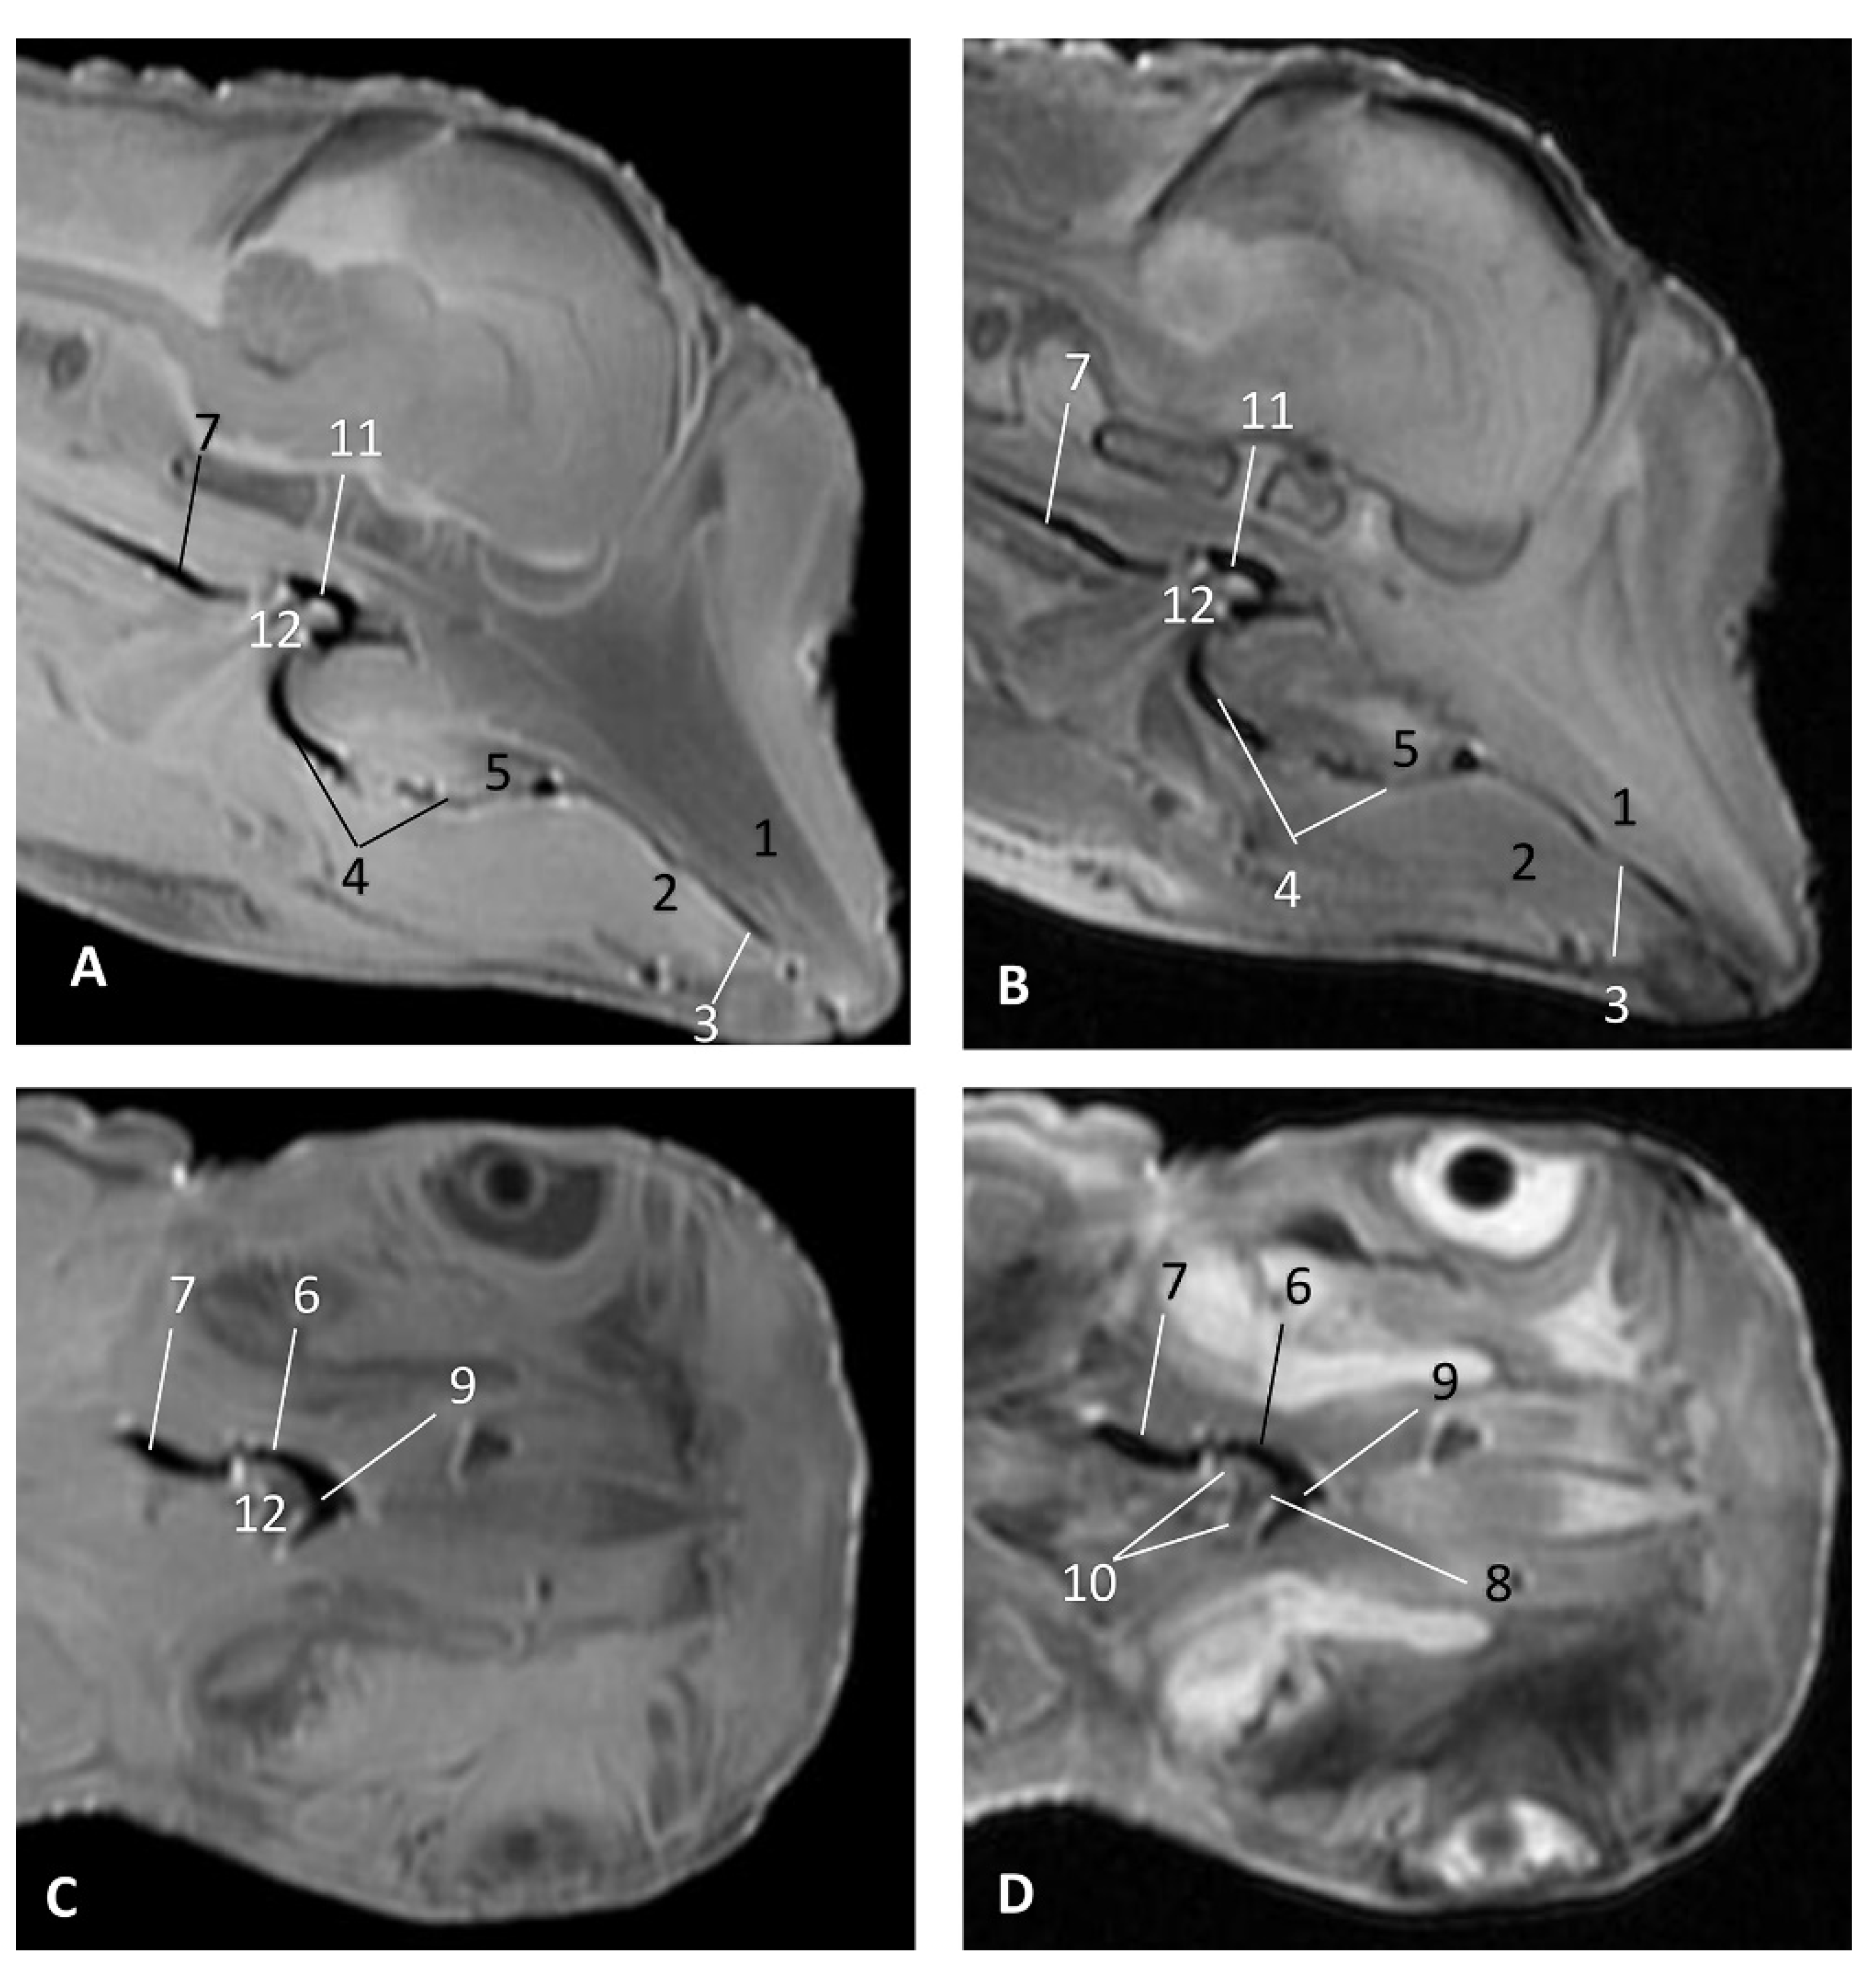

MRI Study

The MRI sagittal images show a pharyngeal cavity in a Globicephala melas fetus (gma1) and we could appreciate the oropharynx (fauces), the nasopharynx and the oesophageal vestibule hypointense in both T1 and T2 sequences(Figure 25A,B). Coronal T1 and T2 sequences show the piriform recess alongside the larynx (Figure 25C,D).

Figure 25.

Images of the oral and pharyngeal cavity. MR sagittal and coronal images are oriented so that the rostral is to the right. (A) T1 SE sagittal, (B) T2 FrFSE sagittal, (C) T1 SE coronal and (D) T2 FrFSE coronal planes. 5 months, gma1. 1, Hard palate; 2, Tongue; 3, Oral cavity (closed); 4, Oropharynx: fauces; 5, Oropharynx: soft palate; 6, Laryngopharynx: left piriform recess; 7, Laryngopharynx: oesophageal vestibule; 8, Epiglottis cartilage; 9, Epiglottic vallecula; 10, Arytenoid cartilages; 11, Nasopharynx; 12, Larynx.

In MRI, we can appreciate, in early fetal stages, a bilateral structure within the laryngopharyngeal cavity, each named as a pharyngeal diverticulum of the auditory tube (PDAT). These are connected through the musculotubaric channel with the middle ear (temporal bone: petrous and tympanic part). In a young Delphinus delphis fetus (dde3), it appears in sagittal sections as a hyper/hypointense area seen caudal and rostrally, respectively (Figure 26A,B), and also in coronal sections (Figure 26C,D).

Figure 26.

Images of the pharyngeal cavity. MR sagittal and coronal images are oriented so that the rostral is to the right. (A) T1 SE sagittal, (B) T2 FrFSE sagittal, (C) T1 SE coronal and (D) T2 FrFSE coronal planes. 4 months, dde3. 1, Inner and middle ear; 2, Pharyngeal diverticulum of the auditory tube.

In older Delphinus delphis fetuses (dde5, dde8, dde11) this double space at both sides of the laryngopharynx is more evident and shows the same intensity, but now we can distinguish the vascular area (hyperintense) and the air-filled area (hypointense) (Figure 27, Figure 28, Figure 29, Figure 30 and Figure 31).

Figure 27.

Images of the pharyngeal cavity. MR coronal and sagittal images are oriented so that the rostral is to the right. (A,B) T2 FrFSE sagittal, (C) T1 SE and (D) T2 FrFSE coronal planes. 5.5 months, dde5. 1, Inner ear; 2, Pharyngeal diverticulum of the auditory tube: moderate hyperintense area (vascular); 3, Pharyngeal diverticulum of the auditory tube: hypointense area (air).

Figure 28.

Images of the pharyngeal cavity. MR sagittal and coronal images are oriented so that the rostral is to the right. (A) T1 SE sagittal, (B) T2 FrFSE sagittal, (C) T1 SE coronal and (D) T2 FrFSE coronal planes. 6 months, dde8. 1, Inner ear; 2, Pharyngeal diverticulum of the auditory tube: moderate hyperintense area (vascular); 3, Pharyngeal diverticulum of the auditory tube: moderate hypointense area; 4, Pharyngeal diverticulum of the auditory tube: hypointense area (air); 5, Pharyngeal diverticulum of the auditory tube: hyperintense area (vascular).

Figure 29.

Images of the pharyngeal cavity. (A,B) MR coronal and sagittal images are oriented so that the rostral is to the right. (A,B) T2 FrFSE coronal and sagittal planes. 8 months, dde11. 1, Oropharynx: fauces; 2, Nasopharynx; 3, Laringopharynx: oesophageal vestibule; 4, Nasopharynx: pharyngeal diverticulum of the auditory tube; 5, Pharyngeal diverticulum of the auditory tube: hyperintense area (vascular); 6, Pharyngeal diverticulum of the auditory tube: hypointense area (air); 7, Larynx; 8, Middle and inner ear.

Figure 30.

Images of the pharyngeal cavity. MR sagittal and coronal images are oriented so that the rostral is to the right. (A) T1 SE sagittal, (B) T2 FrFSE sagittal, (C,E) T1 SE coronal and (D,F) T2 FrFSE coronal planes. 4 months, dde14. 1, Inner and middle ear; 2, Pharyngeal diverticulum of the auditory tube (vascular); 3, Pharyngeal diverticulum of the auditory tube (air); 4, Auditory tube; 5, Nasopharinx; 6, Intrapharyngeal orifice.

Figure 31.

Images of the pharyngeal cavity. MR sagittal and coronal images are oriented so that the rostral is to the right. (A) T1 SE sagittal, (B) T2 FrFSE sagittal, (C) T1 SE coronal and (D) T2 FrFSE coronal planes. 9 months, grgr1. 1, Inner and middle ear; 2, Pharyngeal diverticulum of the auditory tube: vascular; 3, Pharyngeal diverticulum of the auditory tube: air; 4, Mandibles.

In more advanced fetal development, it is possible to observe air (hypointense) and vascular (moderate hyperintense) areas, and even the auditory tube (slightly hypointense) (Figure 30).

PDAT were clearly seen in sagittal and coronal sections in a Grampus griseus fetus (grgr1). The T2 sequences are clearer than T1 because they differentiate two areas: slightly hypointense (vascular) and hyperintense (air) (Figure 31).